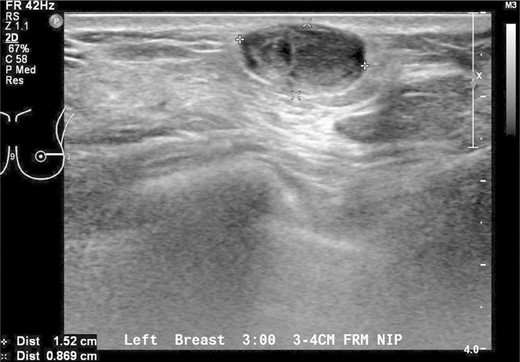

Our patient underwent an excisional biopsy without a preoperative needle biopsy. A 1.2 × 1.2 × 0.8 cm smooth well-encapsulated nodule was removed in entirety from the breast parenchyma. On bisection, the cut section displayed a pale pink smooth homogeneous appearance. Microscopic evaluation showed an encapsulated spindle cell tumour with prominent nuclear palisading and features typical of a schwannoma (Fig. 3). There was also strong and diffuse positive staining of S-100, favouring the diagnosis of schwannoma (Fig. 4). There was no evidence of malignancy in the specimen.

Immunohistochemistry showing tumour cells staining strongly and diffusely for S-100 protein.

Macroscopically, breast schwannomas are described as white, grey, tan or pink well-encapsulated masses. Microscopically, they are spindle cell tumours with Antoni A patterns (hypercellular areas with palisading nuclei surrounding pink areas called Verocay bodies) and Antoni B patterns (hypocelluar regions with looser stroma and myxoid change) Schwannomas almost always stain positive for S100 protein. A cytologic diagnosis via fine needle aspiration may be possible if clusters of spindle-shaped cells arranged in a palisading fashion and lacking epithelial elements are seen [3].